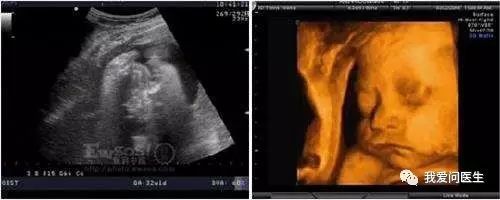

孕期B超检查可以诊断出宝宝的生长发育是否正常、有没有畸形、胎盘的位置是否适合自然分娩等情况。但是,准妈妈在整个孕期应该做几次B超?阴道B超是否会导致流产?B超检查结果绝对可靠吗?它是否对胎儿足够安全?《健康加油站--人口直通车》邀请北京世纪坛医院超声科主任、主任医师 杨敏带您一起来了解一下孕期超声那些事儿。

3 医生开的是彩超,为啥超声屏幕是黑白的?

超声与彩电的原理不同哦。对于孕期超声检查来说,只有在测量胎心率和脐血流的时候才会显示红色和蓝色的血流,才会有所谓的彩色,而不是大家想象当中胎儿是彩色的。